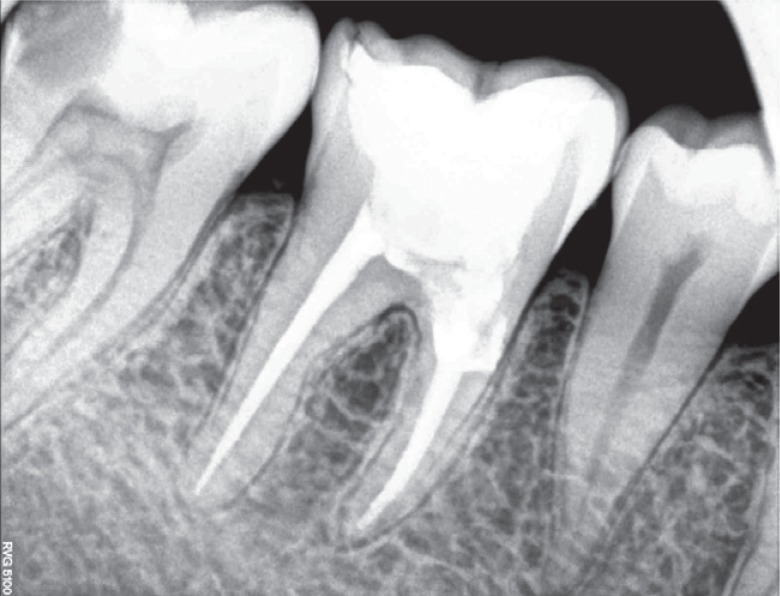

A 25 year old female patient presented to the Department of Conservative Dentistry and Endodontics with a chief complaint of pain in the region of the mandibular right first molar. She reported that an emergency access opening was performed one week prior for the same. Upon clinical examination, extensive destruction of the coronal tooth structure was noted (

Figure 1). Radiographic analysis revealed a periapical radiolucent lesion around the mesial and distal root of tooth #46, and the periradicular dentin at the coronal third of the mesial root was compromised as a result of the poor endodontic access cavity (

Figure 2Preoperative radiograph revealing a periapical radiolucent lesion in the region of the mesial and distal root of tooth #46, as well as compromised periradicular dentin at the coronal third of the mesial root due to a poor endodontic access cavity.